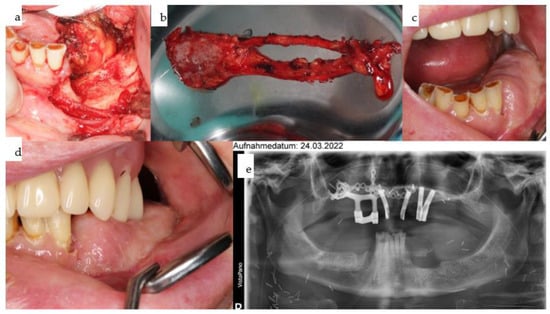

For over 5.5 years, the dental rehabilitation concept has been fully functional, combining conventional dental implants with a secondarily placed patient-specific rigidly fixated subperiosteal implant, allowing retention of the main aspect of the original implant-borne concept (i.e., four dental implants) and full functional reconstruction of the ablated area without bone augmentation using an IPS Implants® Preprosthetic. In 2022, the patient developed another squamous cell carcinoma in the left premolar gingival region of the mandible (Figure 12), necessitating further treatments and reconstructions.

2.2.6. Subsequent Treatments

Marginal resection was performed, with alveolar bone removal posterior to the lower left canine followed by primary reconstruction using a microvascular prelaminated fasciocutaneous radial forearm flap (prelamination was provided by re-blepharoplasty of the upper eyelids), allowing separation of the horizontal (floor of the mouth) from the vertical (vestibule, lip, cheek) subunits (Figure 13 and Figure 14). Following final histopathology confirming R0 resection, a CAD/CAM subperiosteal implant was inserted 11 months later onto the left lateral mandible, with a boom running over the left mental foramen and projecting far posteriorly, while another boom was designed over the chin to the contralateral side, respecting the tooth roots (Figure 15). Multivector rigid fixation was provided by 17 2.0 screws ranging from 7 to 13 mm in length. Simultaneously, two conventional bone-level dental implants were inserted using guided surgery with a CAD/CAM drill guide designed with coDiagnostiX® 10.3 Software (Straumann, Basel, Switzerland). Twelve months later, the patient developed a fourth onset of squamous cell carcinoma of the anterior mandible, necessitating further marginal resection, including the remaining dentition of the mandible. Another microvascular radial forearm flap was used to reconstruct the intraoral tissues and separate the aforementioned subunits (Figure 16). Only the provisional prosthesis on the IPS Implants® Preprosthetic, together with the implant-borne overdenture in the maxilla, allowed retention of the occlusal relationship and definition of the vertical height.

Figure 12. (a,b): In 2022, a secondary squamous cell carcinoma developed in the left mandibular canine to second premolar region (b). Maxillary form and function are fully compensated for with the removable hard-palate free overdenture in place (a).

Figure 14. (ae): Intraoperative view after tumor ablation due to mucosal cancer around the left canine-to-second-premolar region with marginal resection of the mandible (a); the prelaminated left radial forearm is harvested together with the cephalic vein prior to microvascular anastomosis (b). Twelve weeks post-resection and reconstruction, the prelaminated radial forearm flap shows a stable epithelialized surface (c,d). The orthopantomogram shows the marginal resection with numerous titanium microclips used for hemostasis during previous surgeries (e).